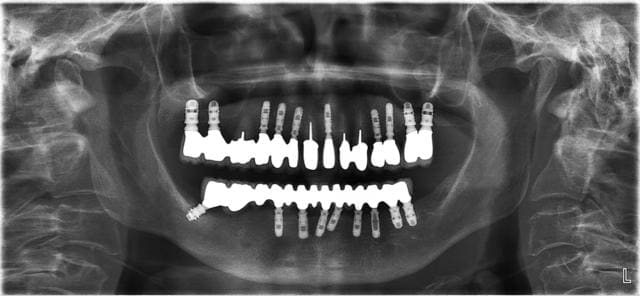

Si la connexion conique ça ne sert à rien, qui peut nous montrer une radio d'implant avec une connexion autre, en fonction depuis quelque temps, et qui ait de l'os à la même hauteur que la connexion ?

Voici 2 panos avec 2 systèmes différents. Dans un cas c'est une connectique hexagone externe en place depuis 1991 le controle date de 2012.

La 2ème est un controle à 3 ans. Seulement voilà les cas d'os au dessus du col ne sont que trop rarissimes et dans des cas tout à fait exceptionnels. Je pense qu'ils dépendent plus de la qualité de gestion que du matos.

Perso: obtenir de l'os au niveau de la connectique est due plus à la vascularisation osseuse qu'à la connectique à proprement parlé, d'où l'importance de la cicatrisation.